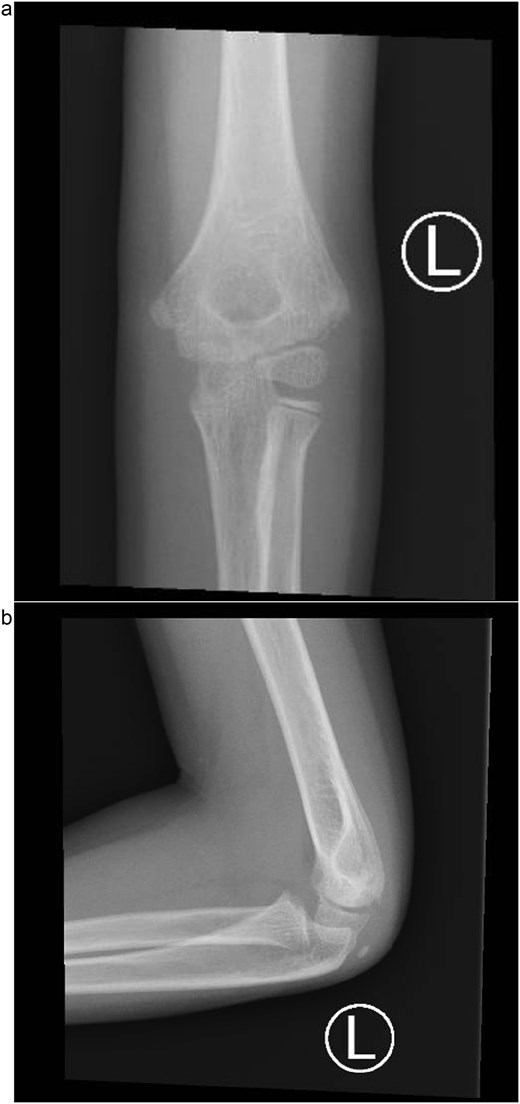

Under procedural sedation, closed reduction of the elbow dislocation was performed, restoring joint alignment and stability. However, post-reduction imaging showed persistent displacement of the lateral condyle fragment (Fig. 2a). The patient was subsequently taken to the operating room, where closed reduction of the condylar fracture was carried out under general anesthesia. As post-reduction displacement was less than 2–4 mm with intact articular cartilage, fixation was performed using two smooth Kirschner wires under fluoroscopic guidance. An arthrogram confirmed joint congruity and cartilage integrity (Fig. 3a). A long-arm posterior slab was applied with the elbow in <90° of flexion to minimize the risk of compartment syndrome (Fig. 4a).

(a) Intraoperative fluoroscopic image following closed reduction and K-wire fixation showing anatomical alignment of the lateral condyle. (b) Arthrogram confirming a congruent articular surface and stable fixation of the fracture fragment.

(a) Postoperative anteroposterior radiograph demonstrating stable fixation of the lateral condyle with two smooth Kirschner wires. (b) Lateral view showing proper wire placement and a well-aligned elbow maintained in a posterior slab splint.